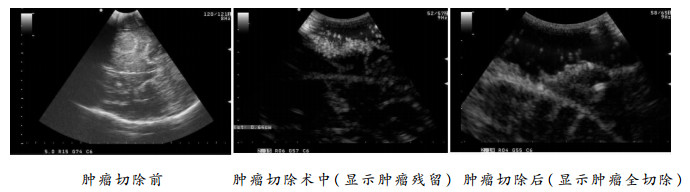

术中彩超由于其操作简便、容易推广、便携等独特优势,已被广泛应用于神经外科手术中[4]。脑胶质瘤手术中利用彩超具有以下优势: (1)能准确定位病灶,测量病变距脑皮层的距离,引导手术路径,避免不必要的损伤;(2)可提供实时图像,可纠正由于术中脑组织移位而引起定位偏差的问题;(3)能确定脑胶质瘤边界,对低级别胶质瘤更有价值[5];(4)术中可多次反复扫描与切除前超声影像对比,以此来监测病灶的切除情况[6]。在本组患者中,分离外侧裂前常规彩超扫描,确定出肿瘤的大小、深度、范围、与周边结构的关系,并以此确定分离打开外侧裂的范围。术中根据解剖和临床经验判断肿瘤切除情况出现困难时,可利用术中彩超对肿瘤切除的程度进行评估,必要时可与术前超声图像进行对比。如果发现肿瘤残留,可再次明确残余肿瘤的大小、位置、深度等情况,从而指导再次切除,这样可多次术中彩超监测肿瘤切除情况直至肿瘤最大程度的安全的切除(见图 3)。但是超声的图像易受到出血、空气等影响,同时操作者、仪器设备也影响了术中超声的判断[7]。如出现不易判断是否肿瘤残留,应仔细对比术前超声图像加以判断,同时应根据术前影像学分析、肿瘤组织与正常组织的差异、术中电生理监测等综合判断。虽然术中彩超的实时图像与术中磁共振图像相比存在不直观、较易受干扰等不足,但术中彩超能减少肿瘤的残留及提高肿瘤的全切率,仍不失为一种有效的安全的易普及的辅助手术技术。应用神经导航可以准确定位出病灶的位置、范围及边界,并能根据病变位置设计到达病灶区域最短路径。但本组手术均采用经侧裂入路,手术切口、入路也相对固定,无需根据神经导航来设计。另外,侧裂打开后脑脊液流出而引起脑移位,同时随着肿瘤的切除,脑移位越来越明显,如果没有术中的实时图像数据(如术中磁共振),神经导航图像将会产生明显的漂移,这样神经导航在术中就会失去相应的作用。术中彩超提供的是实时图像,很好的解决了这一问题。

|

| 图 3 术中肿瘤切除前、中、后彩超 |